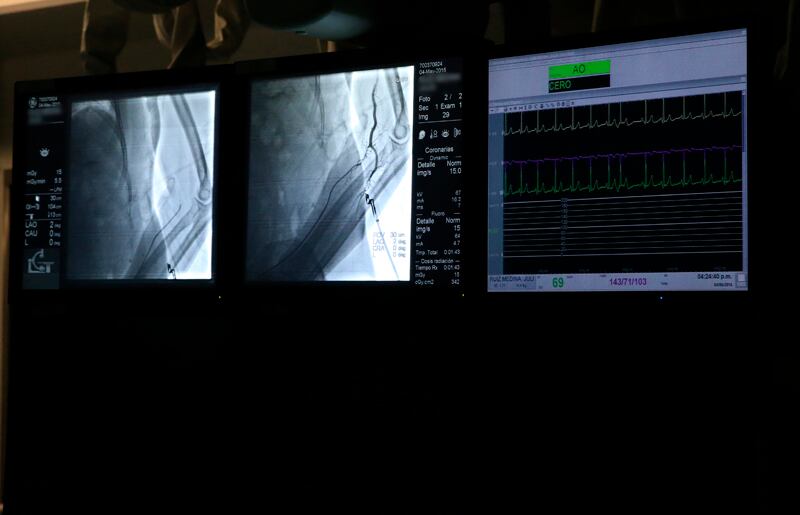

Los hemodinamistas examinan el estado de los vasos sanguíneos y del corazón, mediante procedimientos invasivos de diagnóstico, como es el caso de los catéteres.